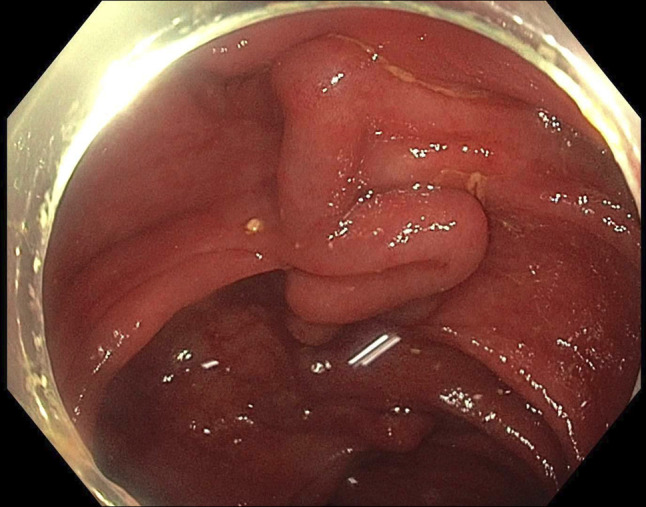

由于特发性结肠静脉曲张(ICV)引起的下消化道出血是非常罕见的。我们报告一位66岁男性复发性尿血,但没有肝脏疾病或门静脉高压症病史。结肠镜检查显示整个结肠有广泛的静脉曲张。没有生化或放射学证据表明肝硬化或门静脉高压症。ICV的潜在病因尚不清楚,在没有标准化治疗方案的情况下,这种疾病的管理具有挑战性。非选择性β受体阻滞剂可以考虑,尽管未知的ICV病理生理和他们的作用在这个临床实体。在我们的病例中,成功的管理包括立即内窥镜治疗和卡维地洛的二级预防。

Lower gastrointestinal bleeding due to idiopathic colonic varices (ICV) is very rare. We present a 66-year-old man with recurrent hematochezia but without history of liver disease or portal hypertension. Colonoscopy revealed extensive varices throughout the colon. There was no biochemical or radiological evidence of cirrhosis or portal hypertension. The underlying etiology of ICV is unknown, and management of this condition is challenging without standardized treatment protocols. Nonselective beta-blockers could be considered despite the unknown ICV pathophysiology and their effect in this clinical entity. The successful management in our case included immediate endoscopic treatment and secondary prophylaxis with carvedilol.